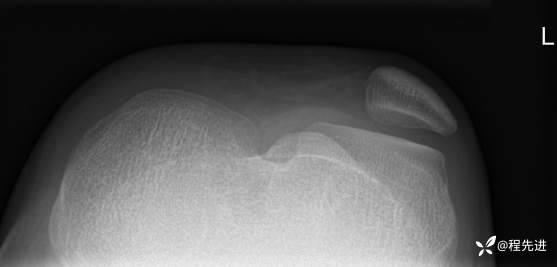

左膝关节正、侧、轴位DR:

img